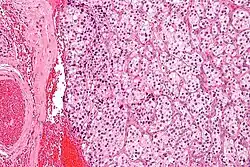

| Micrograph of a carotid body tumor (a type of paraganglioma) | |

The paragangliomas appear grossly as sharply circumscribed polypoid masses and they have a firm to rubbery consistency. They are highly vascular tumors and may have a deep red color.

On microscopic inspection, the tumor cells are readily recognized. Individual tumor cells are polygonal to oval and are arranged in distinctive cell balls, called Zellballen.[9] These cell balls are separated by fibrovascular stroma and surrounded by sustentacular cells.

By light microscopy, the differential diagnosis includes related neuroendocrine tumors, such as carcinoid tumor, neuroendocrine carcinoma, and medullary carcinoma of the thyroid.

With immunohistochemistry, the chief cells located in the cell balls are positive for chromogranin, synaptophysin, neuron specific enolase, serotonin, neurofilament and Neural cell adhesion molecule; they are S-100 protein negative. The sustentacular cells are S-100 positive and focally positive for glial fibrillary acidic protein. By histochemistry, the paraganglioma cells are argyrophilic, periodic acid Schiff negative, mucicarmine negative, and argentaffin negative.

Micrograph of a carotid body tumor Micrograph of a carotid body tumor